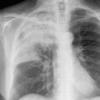

Case 2 Lingular pneum PA

Date: 04/17/2005

Views: 5799